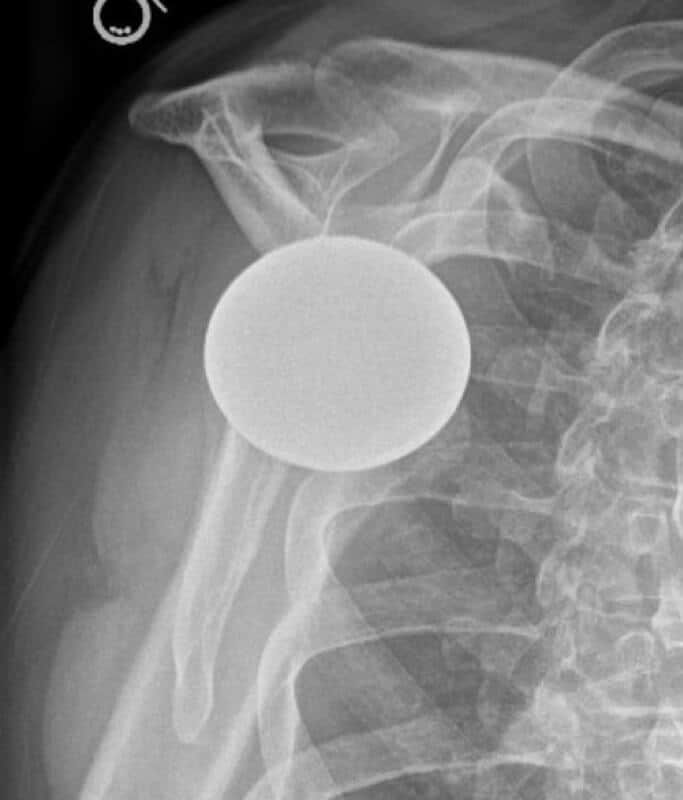

DJO/Enovis, CS Edge